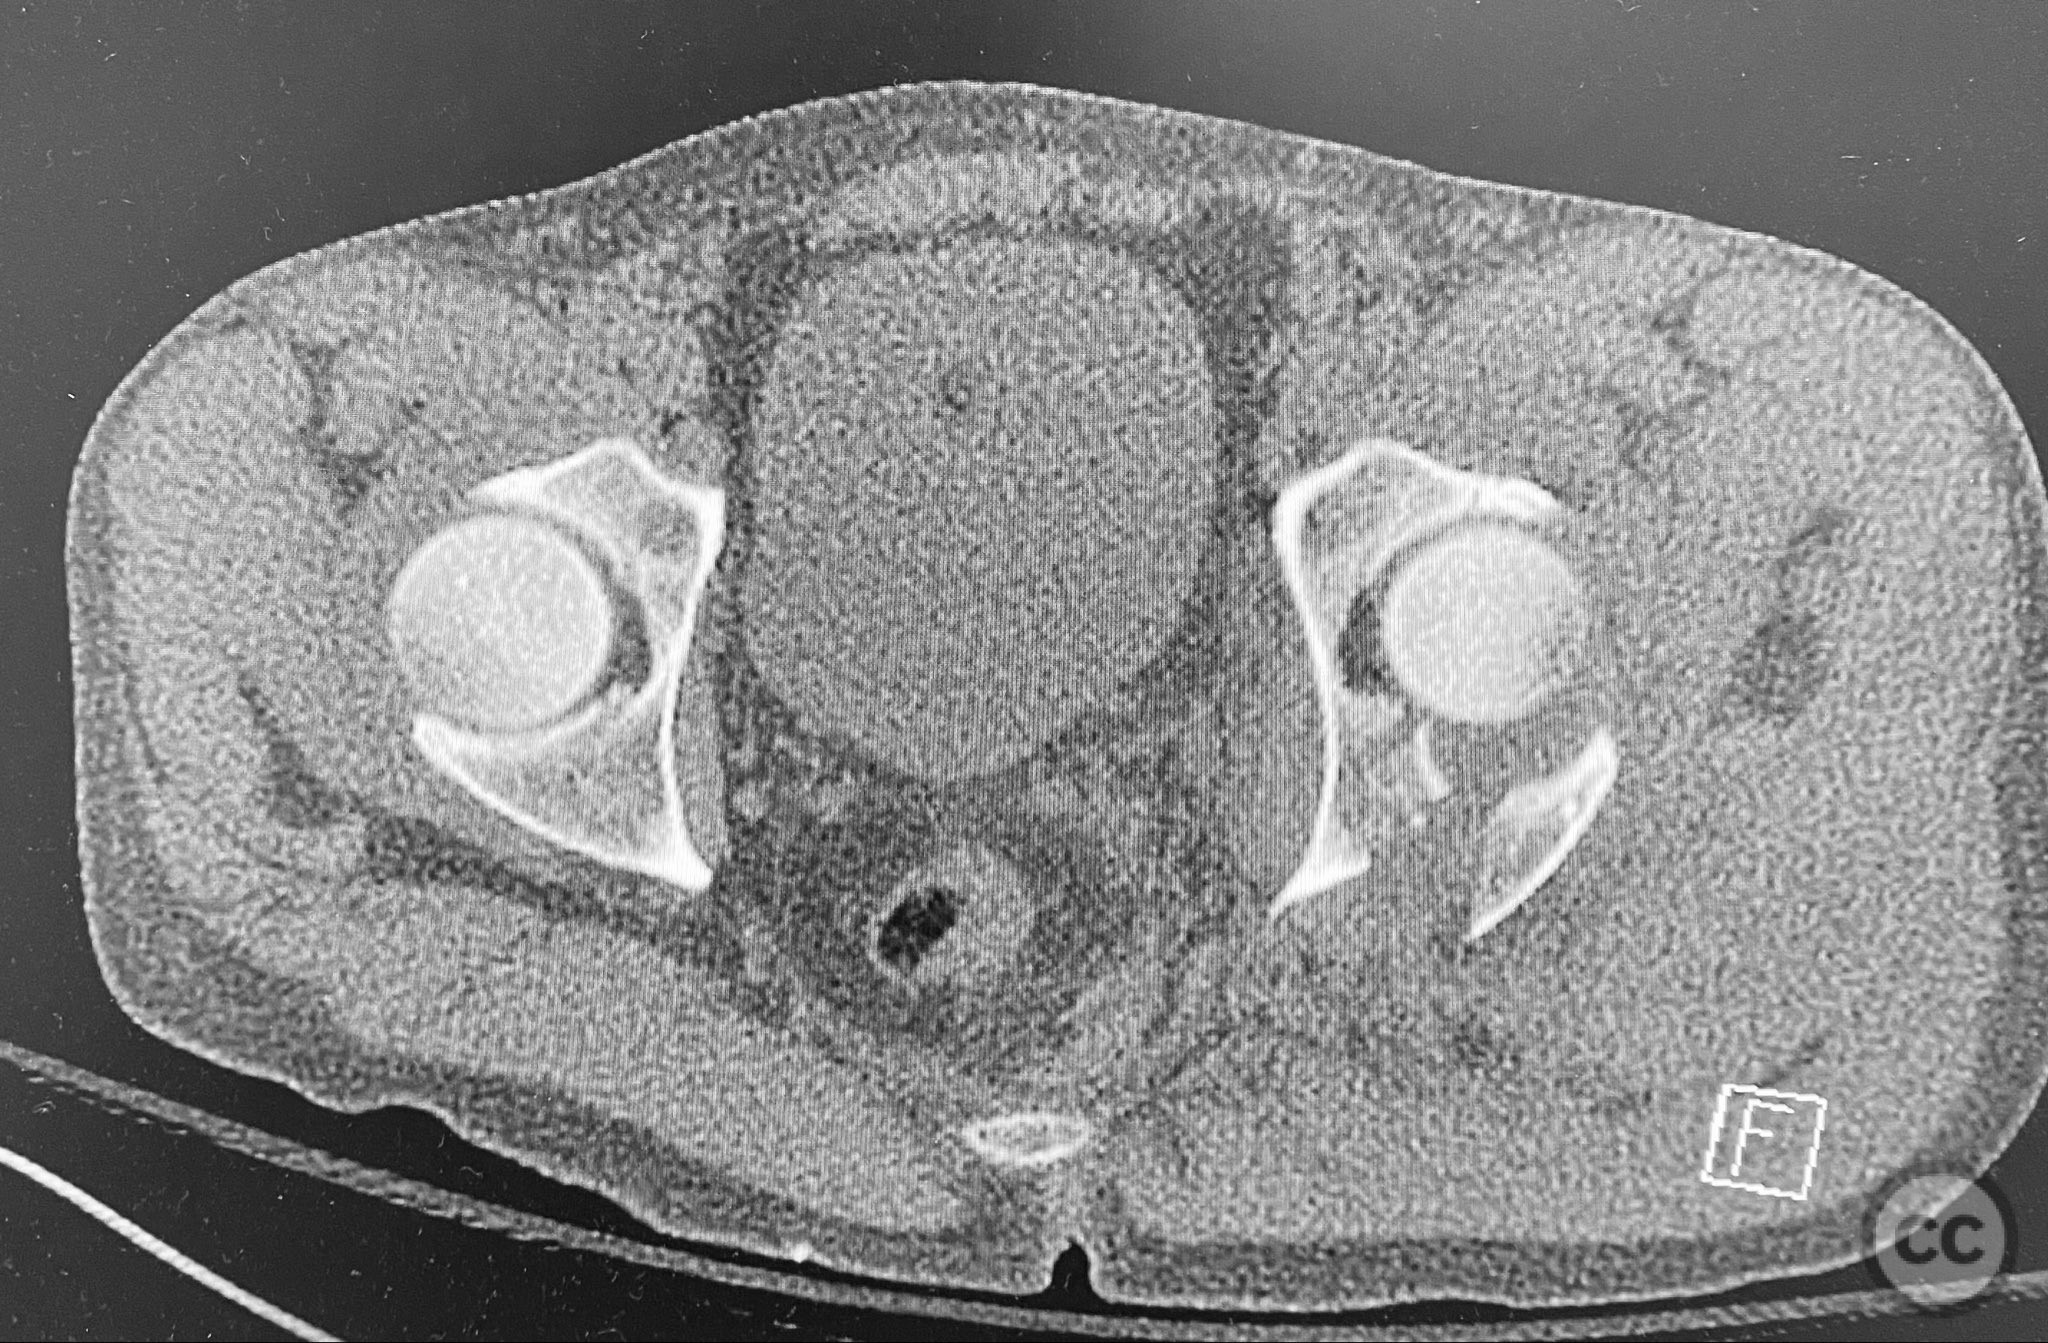

Clinical and radiological findings:  A patient presented with a seemingly non-comminuted, wide, and long posterior wall (PW) acetabular fracture fragment. Axial computed tomography (CT) images demonstrated the thickness of the PW fragment, the articular surface, and multiple areas of subchondral impaction. Preoperative planning identified the size, location, and depth of the impaction zones, as well as an essentially nondisplaced transverse acetabular fracture line, which was not readily apparent on initial imaging. No significant displacement of the transverse component was noted. The AO/OTA classification is 62-B1.3 (posterior wall and transverse acetabular fracture).